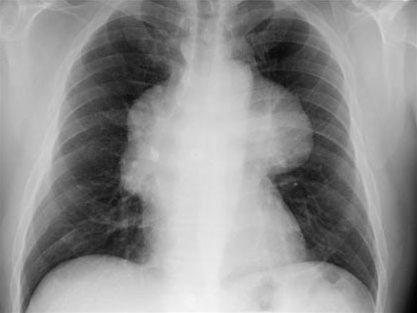

Røntgen af thorax med neoplastisk thymom eller carcinom

• Røntgen af thorax

• Diagnosen kan mistænkes på grundlag af et vanligt thorax-billede, som ofte viser breddeøget mediastinum

• Læsionen viser sig som en glat fortætning i øvre halvdel af thorax, og ligger over den øvre del af hjerteskyggen ved overgangen mellem hjertet og de store kar

• Fortætningen projiceres almindeligvis ind i en af thorax-halvdelene